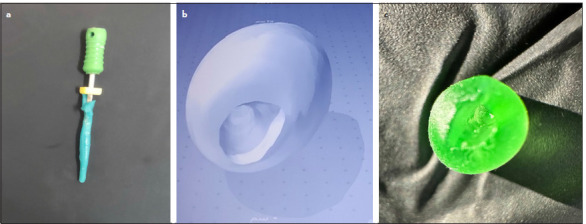

Methods: An impression was captured from the immature premolar root canal, followed by scanning and the subsequent design of prefabricated root canal models for immature permanent teeth (PRCMs). A total of forty PRCM replicas were precision-printed using advanced 3D printing technology. Subsequently, etch PRCM underwent meticulous filling with BioCeramic putty and a fibre post. After two hours, the fibre posts were removed and treated with hydrofluoric acid for all groups. Subsequently, fibre posts of groups except the GIC group received silane solution application. The PRCMs were categorised into four groups based on the cementation system employed: TC Group (n=10), SC Group (n=10), SCB Group (n=10), and GIC Group (n=10). After 48 h, the specimens underwent pull-out strength testing using a universal testing machine, performed along an axis parallel to the longitudinal axis of the fibre post at a crosshead speed of 1 mm/min. Failure modes were scrutinised using a stereomicroscope. The acquired data were subjected to robust statistical analyses, employing one-way ANOVA and Tukey HSD tests with a significance level set at α=0.05.